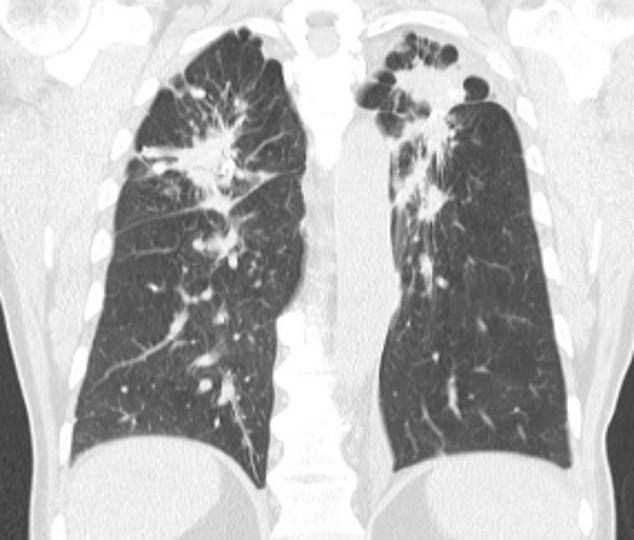

Black lung

DIYers are being warned against installing their own slick stone countertops at home amid the rise of a fatal health condition.